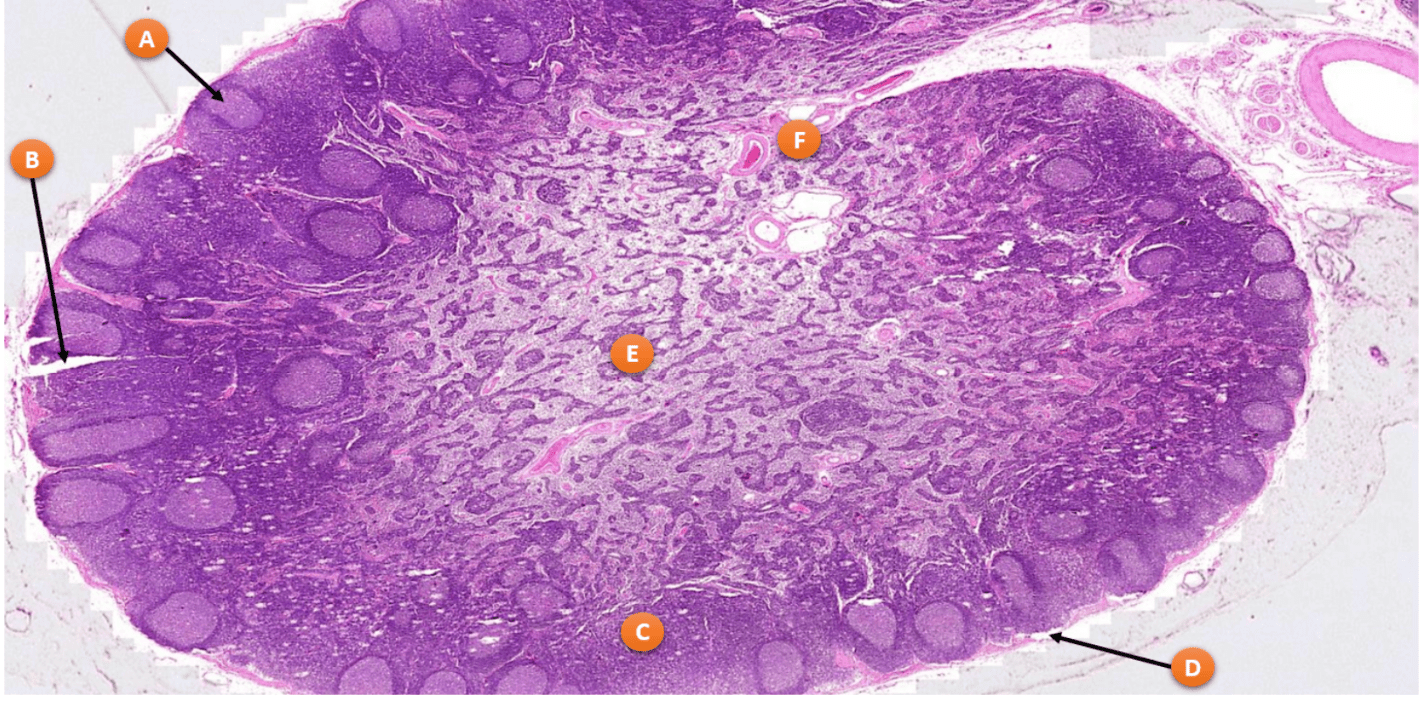

What is the function of the area highlighted by E

Medulla of Lymph Node

Medullary sinuses- antigens are removed by macrophages from slow flowing lymph

Medullary cords: store b cells, plasma cells, dendritic cells and macrophages in reticular fibers

Where t cells form periarterial lymphatic sheaths and where B cells reside in lymphatic nodules

White Pulp